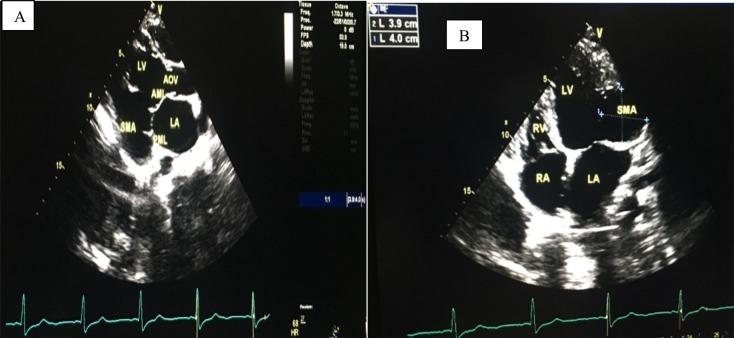

METHODS

In April 2017, a 25-year-old patient havingsubmitral left ventricular aneurysm with New York Heart Association (NYHA) class IV heart failure and mild left ventricular systolic dysfunctionreceived medical treatment at our institution. She had severe mitral regurgitation and aneurysmal thrombus. The diagnosis was easily made using GE Vivid E9 transthoracic echocardiography. She was given drugs for management of heart failure and anticoagulation.